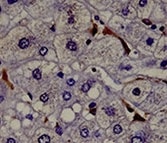

DLL4 in Mouse Embryonic Heart. DLL4 was detected in immersion fixed frozen sections of mouse embryonic heart using Rat Anti-Human/Mouse DLL4 Monoclonal Antibody (Catalog # MAB1389) at 8 µg/mL overnight at 4 °C. Tissue was stained using the Anti-Rat HRP-DAB Cell & Tissue Staining Kit (brown; Catalog # CTS017) and counterstained with hematoxylin (blue). Specific staining was localized to developing cardiomyocytes. View our protocol for Chromogenic IHC Staining of Frozen Tissue Sections.